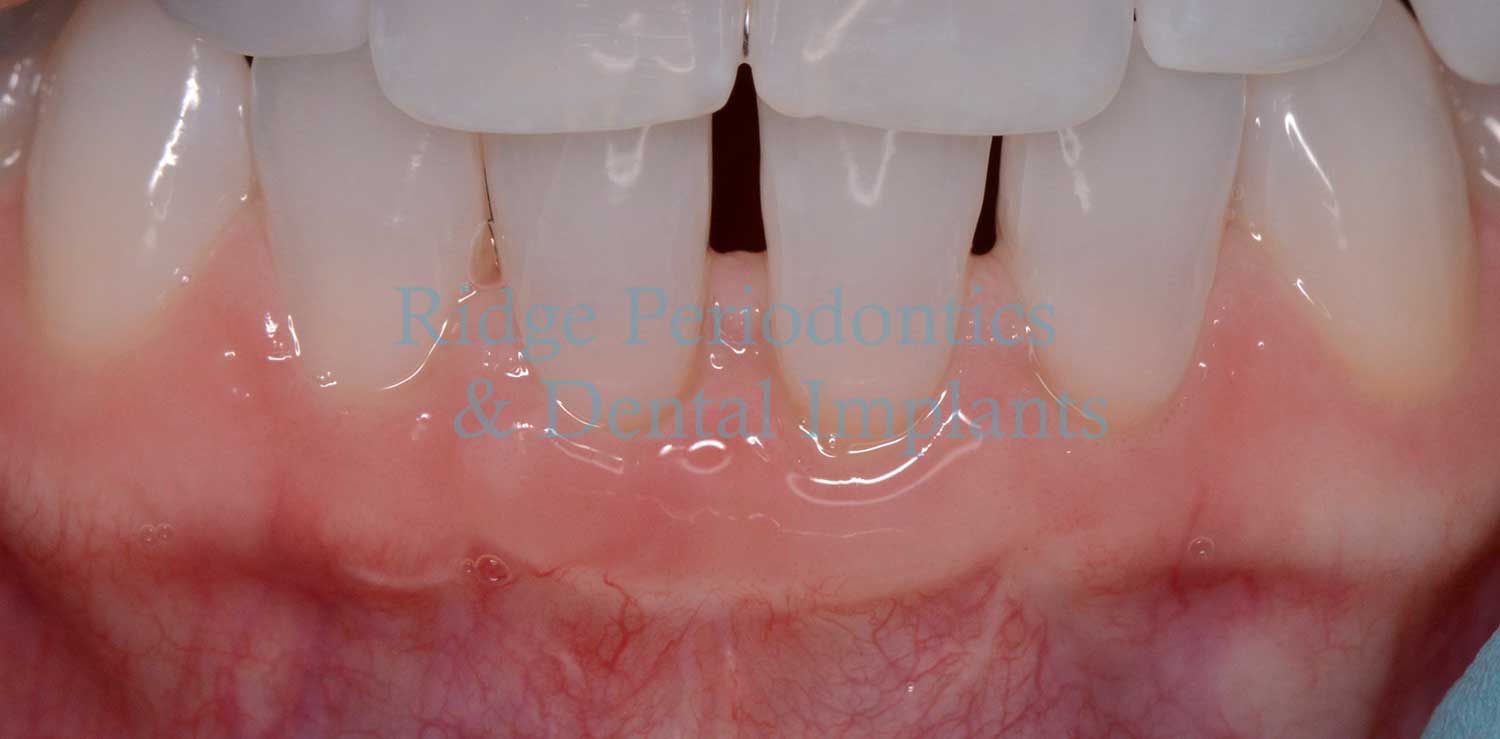

Gum Grafting (Recession)

Soft tissue regeneration “gum grafting” is used to treat gum recession while maintaining natural-looking results.